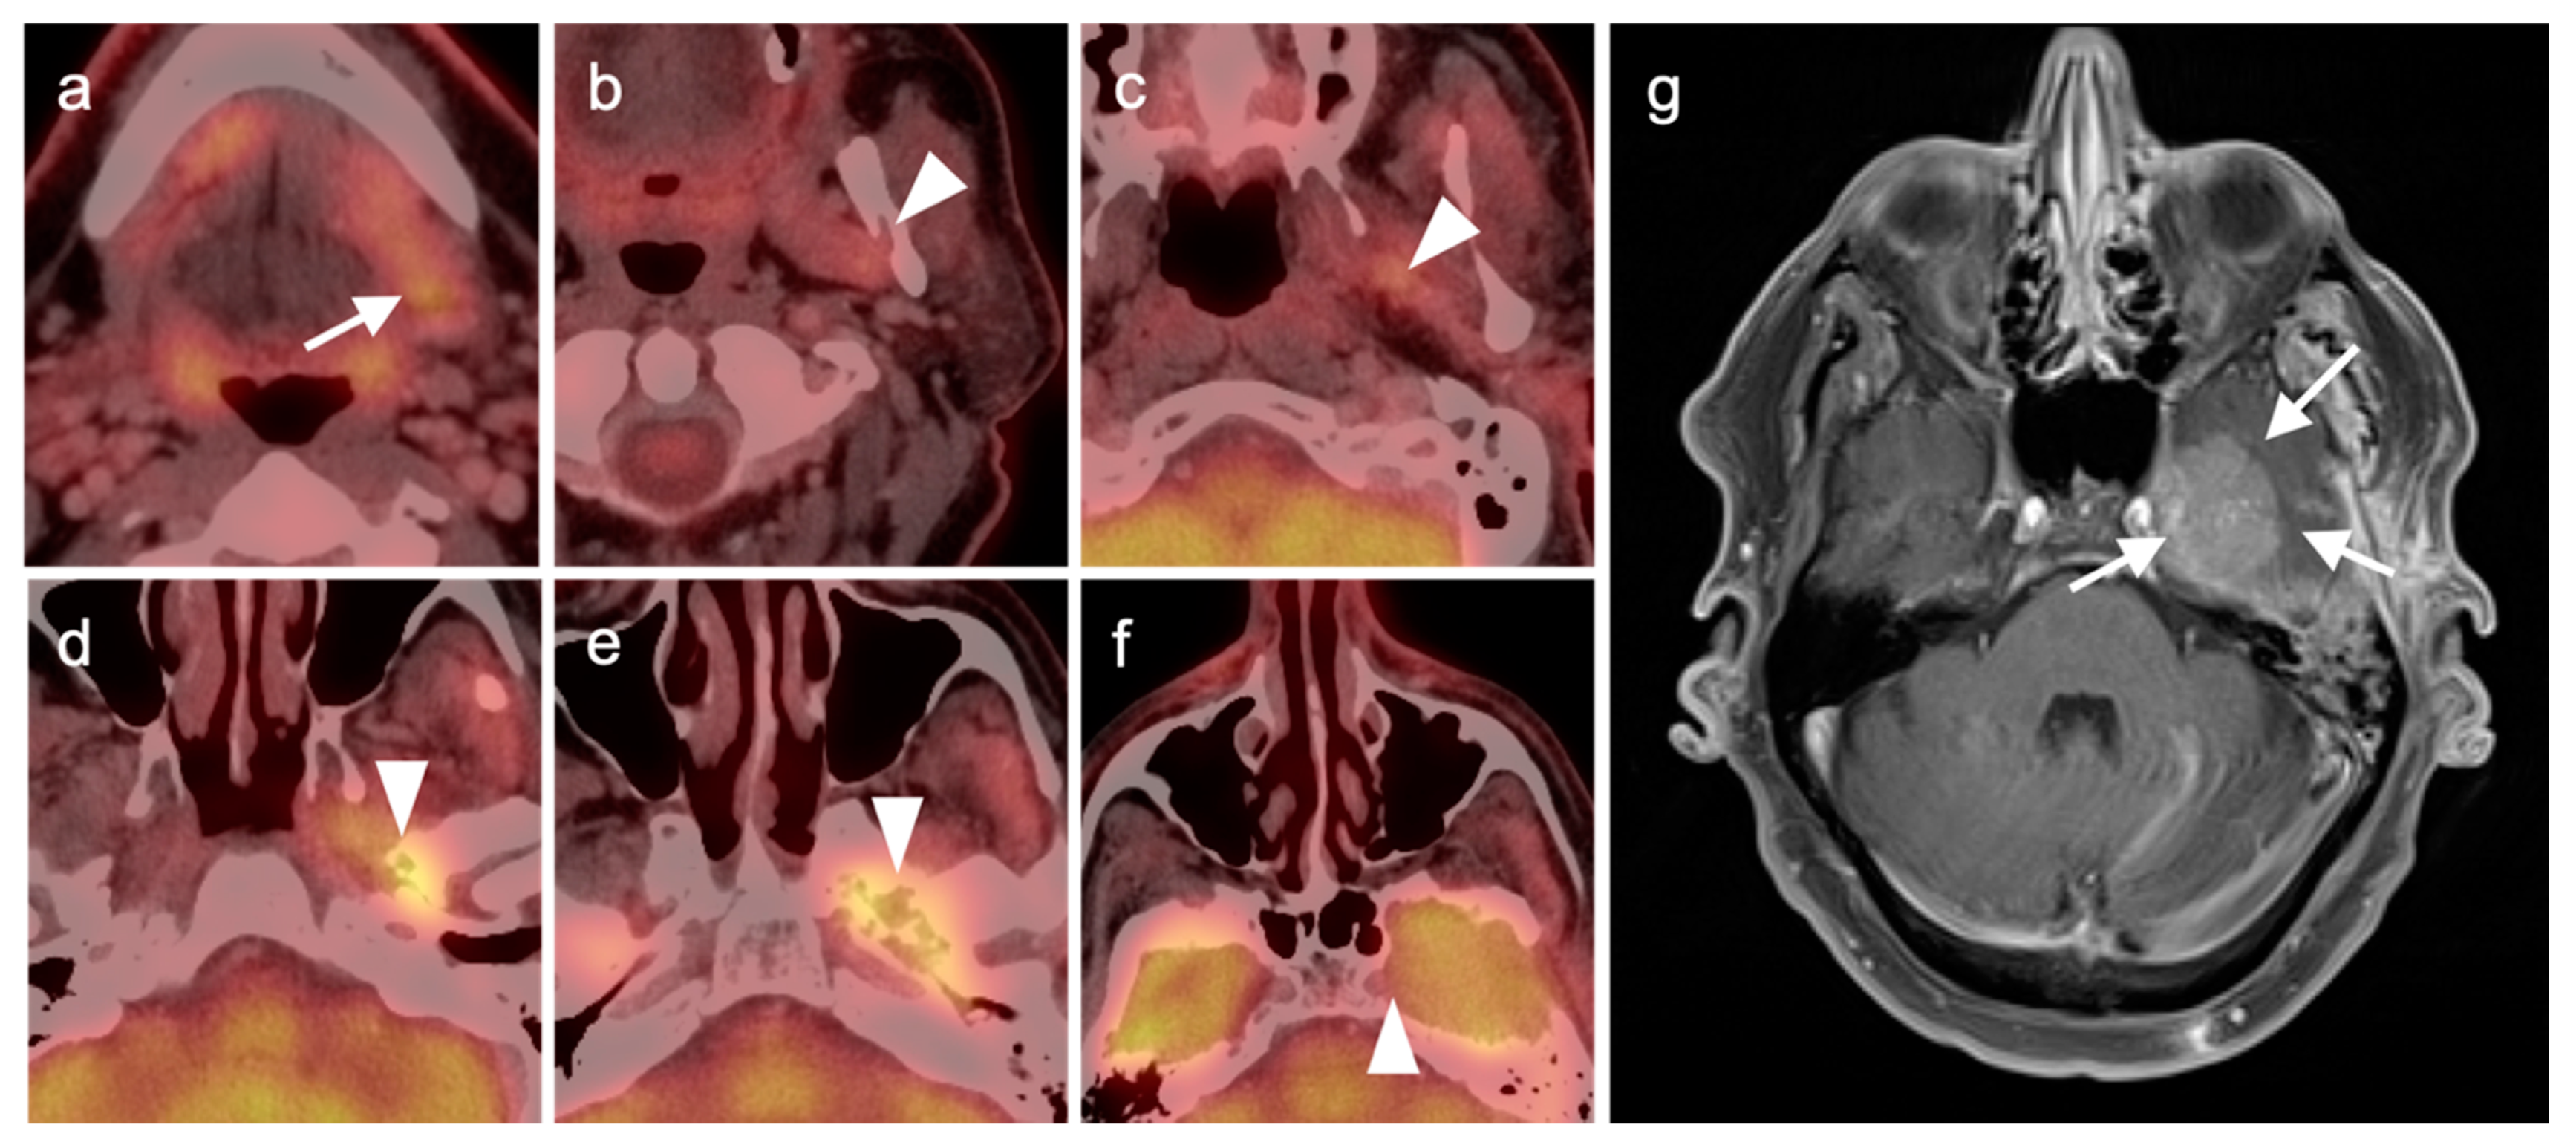

2.3. Nasopharyngeal Carcinoma

2.4. Sinonasal Tumors